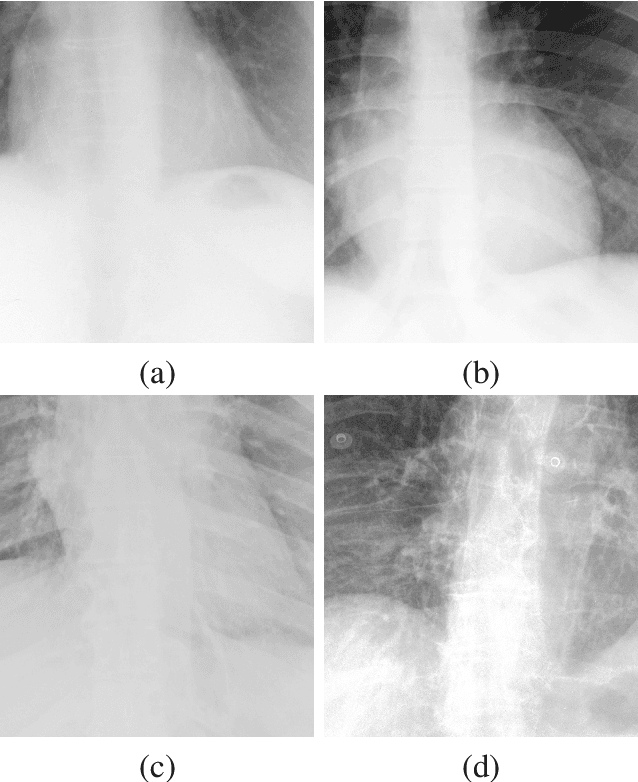

Abstract:X-ray imaging is a fundamental clinical tool for screening and diagnosing various diseases. However, the spatial resolution of radiographs is often limited, making it challenging to diagnose small image details and leading to difficulties in identifying vertebrae anomalies at an early stage in chest radiographs. To address this limitation, we propose a novel and robust approach to significantly improve the quality of X-ray images by iteratively training a deep neural network. Our framework includes an embedded internal guidance layer that enhances the fine structures of spinal vertebrae in chest X-ray images through fully unsupervised training, utilizing an iterative procedure that employs the same network architecture in each enhancement phase. Additionally, we have designed an optimized loss function that accurately identifies object boundaries and enhances spinal features, thereby further enhancing the quality of the images. Experimental results demonstrate that our proposed method surpasses existing detail enhancement methods in terms of BRISQUE scores, and is comparable in terms of LPC-SI. Furthermore, our approach exhibits superior performance in restoring hidden fine structures, as evidenced by our qualitative results. This innovative approach has the potential to significantly enhance the diagnostic accuracy and early detection of diseases, making it a promising advancement in X-ray imaging technology.